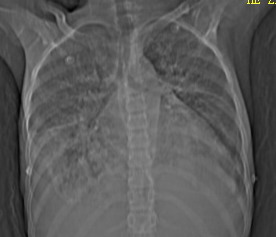

女,12岁,气促、咳嗽2天,3个月前查胸片示:两肺感染,急诊入院查ct,血常规等未检查。

先心(室缺?)、左室大,心功能不全;肺部感染

两肺感染,双侧少量胸腔积液;肺淤血及心脏改变,考虑心功能不全改变。学习了,望能反馈随访结果。

1、左心房、左心室增大,考虑左心衰, 2、肺水肿合并感染 3、双侧胸腔积液

双肺中下野不规则片絮状阴影,中外带明显,双侧胸腔少量积液,心影增大,心腔密度减低,隆突下及左侧气管旁见钙化淋巴结影,考虑双肺感染、心衰;建议结合临床除外h1n1并急性心衰,先心不能排除。